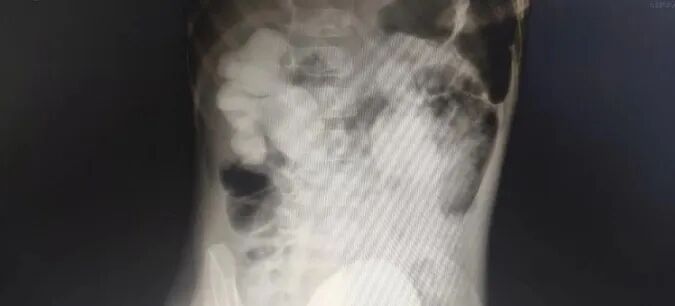

??鲁网11月6日讯 近日,潍坊市人民医院小儿内二科收治了一例特殊的小病人,小朋友因为反复泌尿系感染长期往返于多家医院儿科治疗,均未能明确病因,科室接诊后认为这种复杂泌尿系感染,应首先注意排除膀胱输尿管反流,立即为患儿进行了泌尿系CT+CTU、膀胱输尿管反流等检查,该患儿明确诊断为膀胱输尿管反流(Ⅳ级-Ⅴ级)、重度双肾积水、输尿管狭窄、复杂性泌尿系感染。